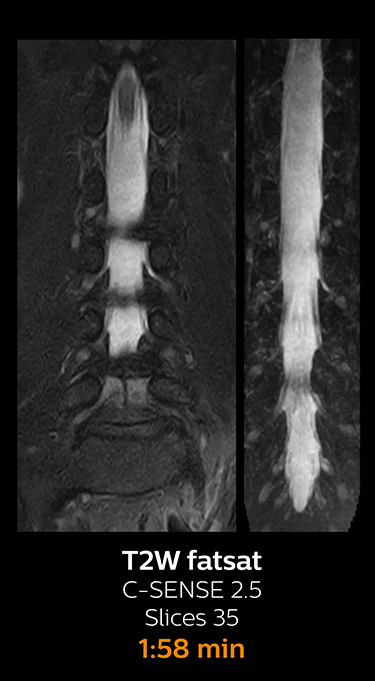

With Compressed SENSE, the scan time for the routine cervical spine examination at KNC was reduced from 13:11 to 9:52 minutes, which corresponds to 25% reduction.

MRI examination of the cervical spine with Compressed SENSE

Ingenia 3.0T CX

Scan time 9:52 min. (was 13:11 min. without Compressed SENSE)